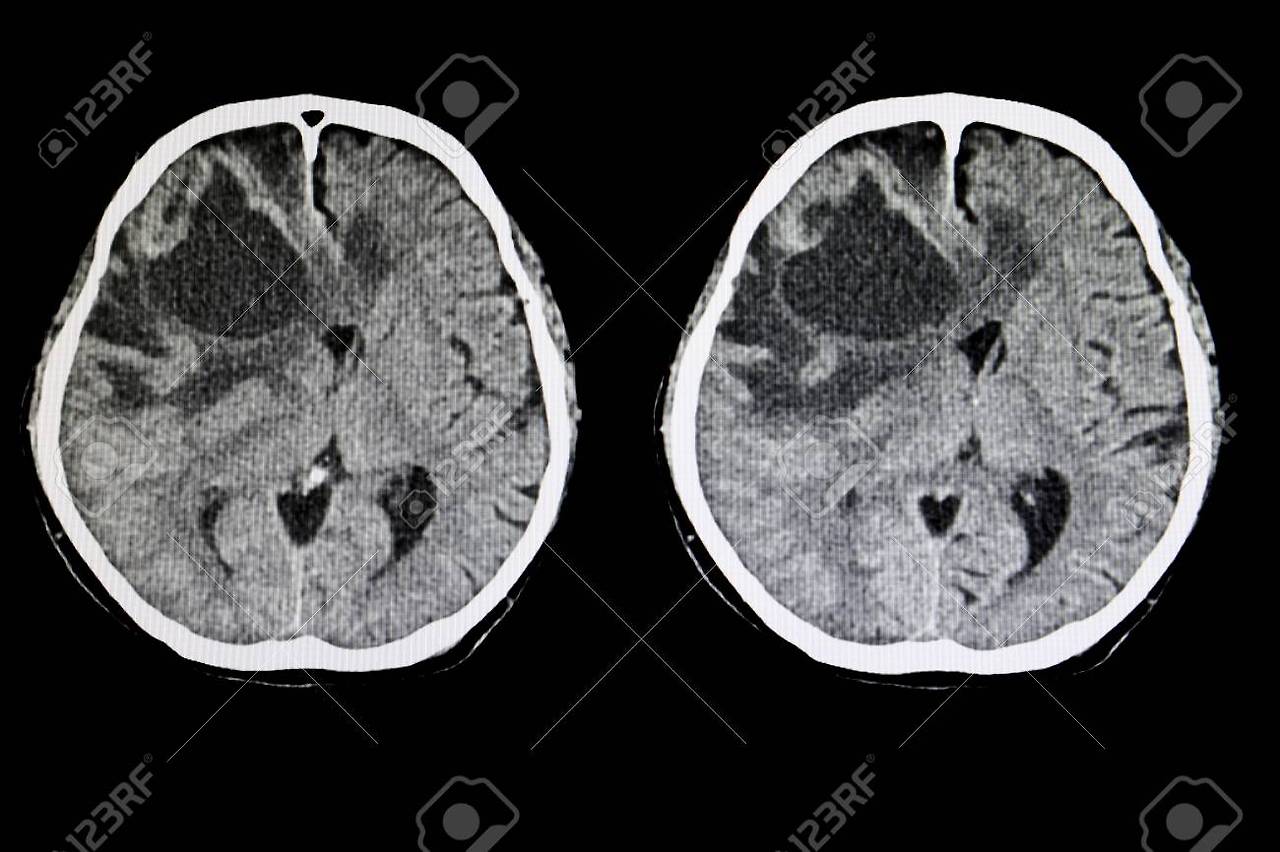

👉 뇌세포 안으로 물이 들어가면서

👉 뇌가 붓는 ‘뇌부종’ 발생

💥 체내 전해질 균형 붕괴 → 뇌부종